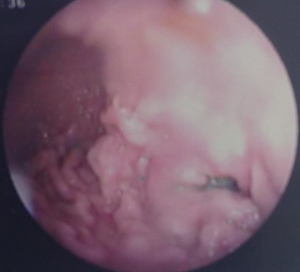

癌の進行状況によって治療は変わっていきます。

症状は時間が経つにつれて悪化していきます。以前は癌というと治療法はなく、亡くなってしまう病気と思われていました。しかし、獣医療の進歩により癌の中には完全に取り除いたり(根治治療)、生涯に渡ってコントロールすることで痛みや苦しみを和らげ(緩和療法)、生活の質(QOL)を保てたりする可能性が広がり、治療も日々変化しています。